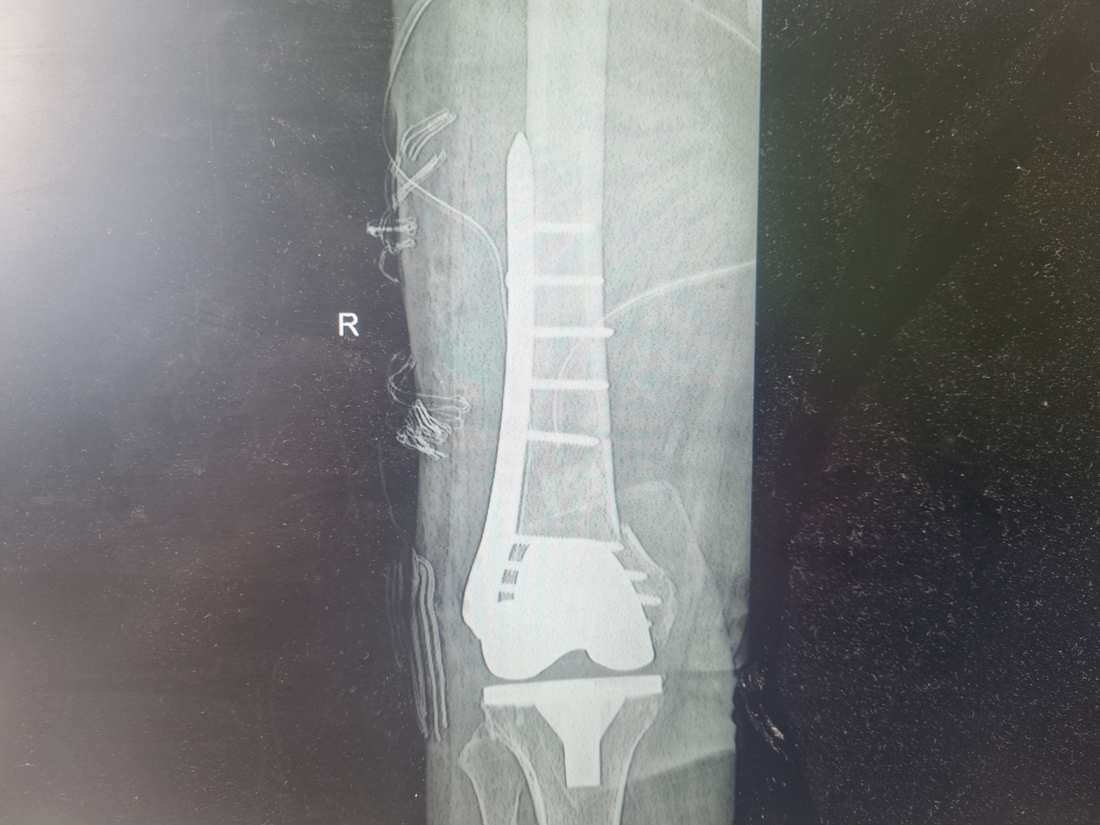

Zabiegi

Moja praca w RTG

Miednica i kończyna dolna